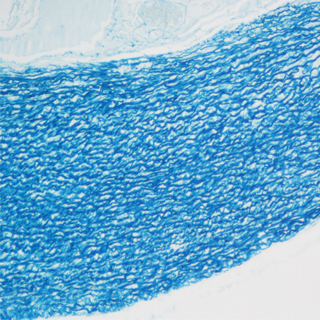

油紅0脂肪染色法是指在日常病理診斷和科研工作中為了顯示組織內的脂肪常采用油紅0進行染色的方法,油紅0為脂溶性染料,在脂肪內能高度溶解,可特異性的使組織內甘油三酯等中性脂肪著色。

實驗結果:

脂滴呈橘紅色至鮮紅色:細胞核呈深藍色。